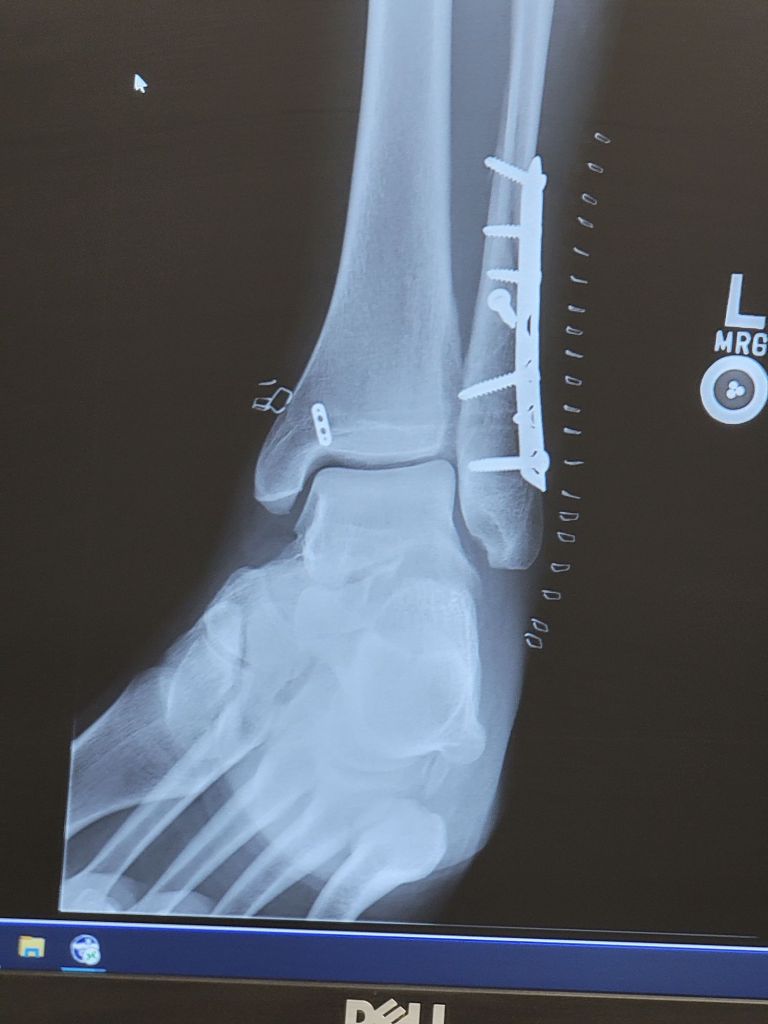

The break was bad enough that it had essentially opened up my ankle joint. If we didn’t fix it properly, I could have long-term issues just walking. A few days later, I was in surgery in Fairbanks, getting everything put back together. Plates, screws, wires… the whole deal.

And all that metal in my ankle now…

That’s my Alaskan souvenir.